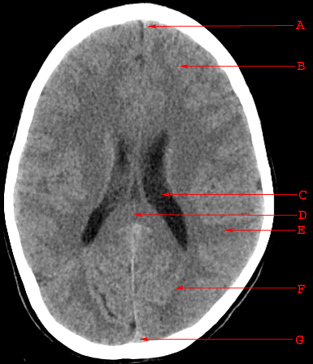

Normal Anatomy

A. Falx Cerebri B. Frontal Lobe C. Body of the Lateral Ventricle D. Splenium of the Corpus Callosum E. Parietal Lobe F. Occipital Lobe G. Superior Sagittal Sinus

A. Falx Cerebri

B. Frontal Lobe

C. Body of the Lateral Ventricle

D. Splenium of the Corpus Callosum

E. Parietal Lobe

F. Occipital Lobe

G. Superior Sagittal Sinus